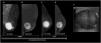

47-year-old male presented with left breast growth for 5 months and unilateral clear discharge. On the low energy images (A, C), a focal asymmetry of the entire upper-external quadrant of the left breast with associated diffuse calcifications are seen. On the recombined images (B, D), a segmental non-mass enhancement is observed. Sonographically (E), the lesion corresponds to a heterogeneous mass. 14G core needle biopsy proved DCIS (F). Histology after mastectomy confirmed pure DCIS with no invasive component.

In males with gynecomastia, detecting DCIS on mammography can be challenging.19 Microcalcifications are seen less likely in male breast cancers, possibly due to the involuted ductal structure.4 When present, these calcifications often have a benign or nonspecific appearance 19 (Fig. 8). Additionally, if invasive carcinoma is present, parenchymal opacity or distortion may be seen.4 DCIS normally presents a non-mass enhancement on the recombined images of CEM (Fig. 9).